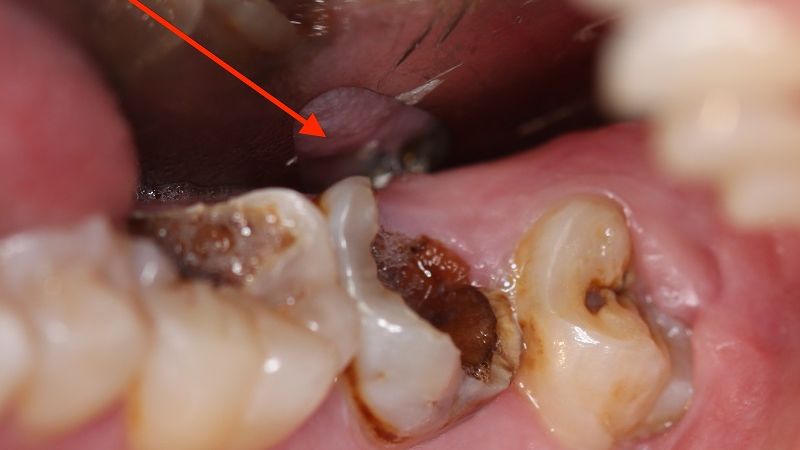

Sâu tủy răng

Sâu tủy răng là mức độ nặng, xảy ra khi vi khuẩn đã xâm nhập vào buồng tủy chứa dây thần kinh và mạch máu. Người bệnh thường đau nhức dữ dội, đau kéo dài về đêm, có thể kèm sưng nướu hoặc áp xe. Khi bị sâu tủy răng việc điều trị thường phức tạp hơn và có nguy cơ mất răng nếu không can thiệp sớm.

Sâu tủy răng là mức độ nặng của bệnh lý sâu răng